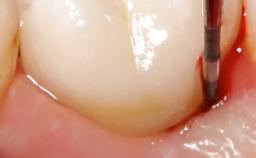

Occlusal Load—a Factor for Implant Failure?

In this case, Nicola Zitzmann describes the sudden loss of a previously well-osseointegrated implant that had been in healthy function for 5 years. The case includes recommendations for occlusion and function of implant restorations. A 74-year-old patient had received implant-fixed dental prostheses in the maxilla in 2008, and in the right mandible three years later. His tooth loss was mainly related to recurrent caries associated with hyposalivation as a potential side effect of his cholesterol-lowering medication.